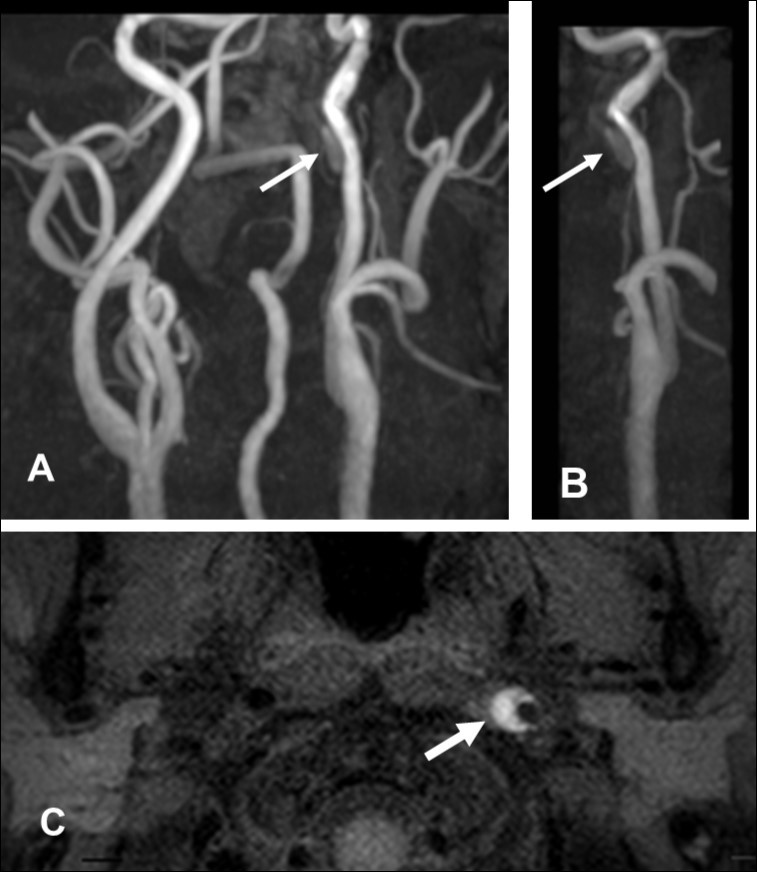

This 43-year-old Japanese male presented with right hand dysesthesia. He has not recognized his neck pain and Horner’s syndrome( oculosympathetic palsy). Magnetic resonance imaging(MRI) performed on a 3T TX scanner (Philips Achieva, The Netherlands) demonstrated dissection of the left cervical carotid artery (CCA; Figure 1A,1B ); no ischemic area was detected in the left cerebral brain. Axial section views of the CCA segment revealed a typical crescent hematoma; a bright, hyper-intense circle representing the narrowed arterial lumen was visualized. A T1-volumetric isotropic turbo spin echo acquisition (VISTA) sequence resulted in the diagnosis of dissection of the CS-ICA (Figure 1C). He had no conventional stroke risk factors such as hypertension, diabetes, hyperlipidemia, a history of cardiac valvular disease, arterial fibrillation, or features of inherited connective tissue disorder. Also absent was a history of arterial trauma and we were unable to identify any etiological factor(s). One week later he developed Gerstman symptoms; border zone ischemia was observed in the left cerebrum (Figure 2-Ic). He was admitted and the administration of antiplatelet agents was started. The left middle cerebral artery (MCA) was supplied via antegrade circulation (Figure 2-Ib) and an increase in the flow-void intensity was noted (compare Figure 1C with Figure 2-Ia). MRI studies acquired one week later revealed spreading of the ischemic area to beyond the watershed zone between the left anterior cerebral artery (ACA) and the MCA, and the MCA and the posterior cerebral artery (PCA) (Figure 2-IIc). The area of dissection had spread from the ICA bifurcation to the top of the ICA. The blood supply to the left MCA territory derived from the circle of Willis (Figure 2-IIb). The flow-void intensity had increased further (compare Figure 2-Ia with Figure 2-IIa). Two weeks after his admission he suddenly experienced complete right-sided hemiparesis with motor aphasia. MRI performed within 45 min demonstrated diffuse ischemia in the left MCA territory (Figure 2-IIIc), the left A1 segment could not be visualized. The left MCA and its A1 segment were completely occluded (Figure 2- IIIb). The flow-void intensity indicated complete occlusion of the true lumen (Figure 2-IIIa). He underwent emergency left superficial temporal artery (STA)-MCA bypass surgery within 6 hours; double anastomosis was successful. External decompression was performed to prevent neurological deterioration due to severe brain swelling. An intensive rehabilitation has been continued for him after operation. His functional independence measure (FIM) score recorded over the course of 4 months showed remarkable improvement ( Figure 3) as did the standard language test for aphasia.

Figure 1.First hospitalization. A. Maximum intensity projection ( MIP )image of arteries in the cervical segment. B. Magnetic resonance angiography of the left carotid artery. C. T1 VISTA sequence. Note the flow void reflective of the narrowed lumen next to intramural hematoma (hyperintense crescent)

First hospitalization. A. Maximum intensity projection ( MIP )image of arteries in the cervical segment. B. Magnetic resonance angiography of the left carotid artery. C. T1 VISTA sequence. Note the flow void reflective of the narrowed lumen next to intramural hematoma (hyperintense crescent)